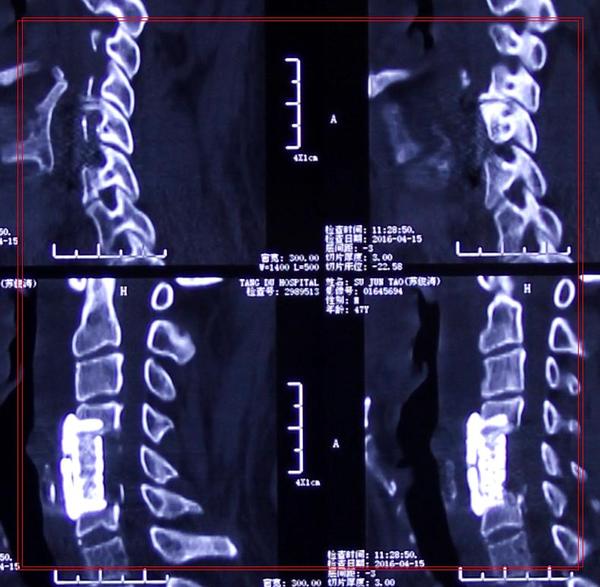

治疗:显微镜下单节段颈椎间盘切除植骨融合内固定术

术后:术后2天,患者四肢麻木、颈肩部不适症状即缓解并可下床活动。同时,心慌胸闷症状完全缓解。

影像学资料